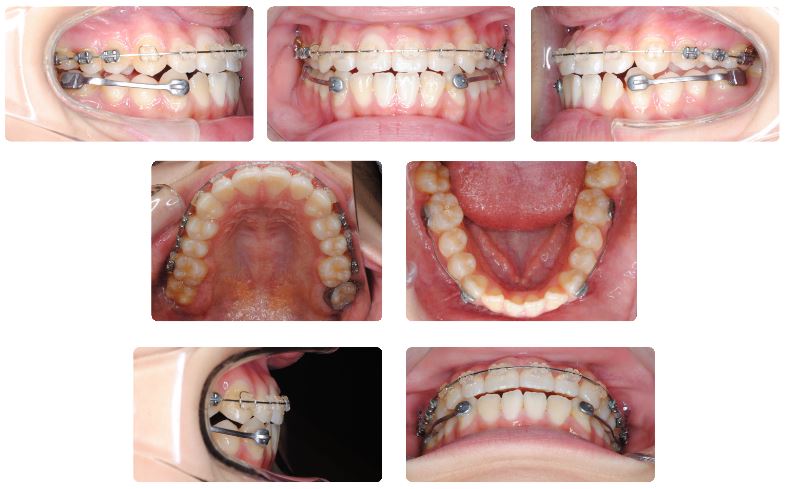

カリエールモーション装着して5か月後の状態です。

上顎は幅径を広げるためにバイパスの拡大装置が装着されています。

下顎にはスペースがみられるようになりました。

現在下顎にマルチブラケット装置を再装着してゴムメタルという素材のワイヤーで治療継続中です。